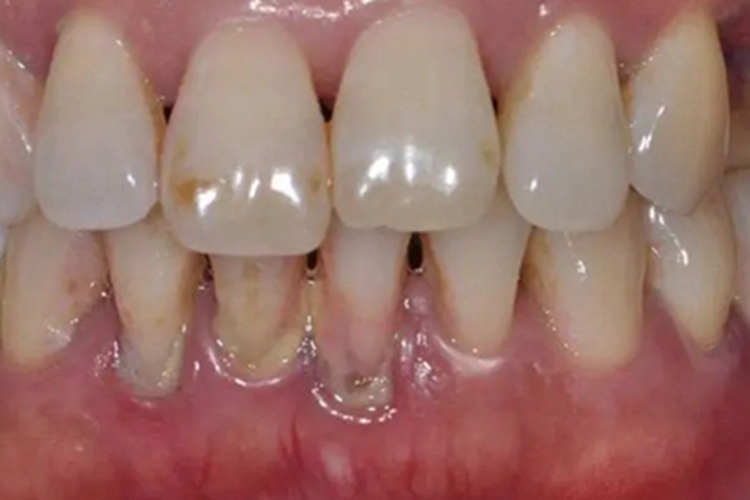

慢性牙周炎的黏膜损害可发生在患者下牙龈,临床可表现为局部黏膜表面出现萎缩,牙龈向牙根方向进行生长,牙齿之间的间隙变大,部分患者还可出现牙齿松动,自觉咀嚼无力或有疼痛感,严重时牙齿可伴有移位等异常。

慢性牙周炎是多因素疾病,可能是由牙菌斑积聚、牙齿不良位置和牙周组织免疫功能低下等原因引起的。细菌和食物残渣附着在牙齿表面,逐渐形成牙菌斑,如果牙菌斑没有及时清除,细菌会引发牙龈炎,进而演变为慢性牙周炎,可导致局部黏膜肿胀,逐渐出现萎缩。